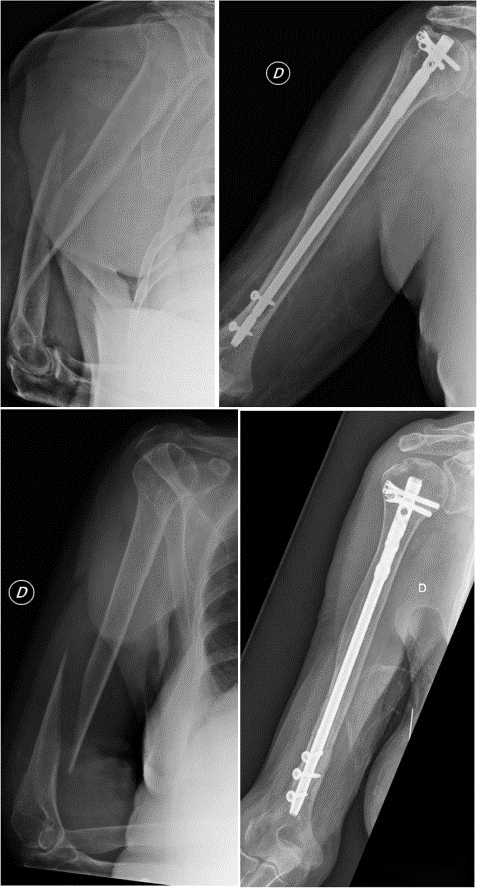

Показания к интрамедуллярной фиксации переломов диафиза плечевой кости в настоящее время расширены, поскольку она менее инвазивна, чем фиксация пластиной. Однако в дистальном отделе плечевой кости имеется множество нервных сосудов, а анатомия относительно сложна. Дистальная фиксация интрамедуллярного стержня увеличивает риск инфекции и повреждения нервов, а также увеличивает время операции и рентгеноскопии.

Поскольку форма кости дистального отдела плечевой кости, по-видимому, подходит для первоначальной стабильности длинного интрамедуллярного стержня, нет ли необходимости в дистальной фиксации для контроля вращения после установки стержня?

Некоторые ученые выдвинули гипотезу, что если во время операции подтверждена достаточная ротационная стабильность, дистальная фиксация длинных IM-стержней не требуется и перелом не затрагивает дистальную треть. Это не влияет на заживление и функциональное восстановление, но сокращает время операции, время рентгеноскопии и риск повреждения нервов.

Ученые сравнили результаты врезки гвоздей с дистальным фиксатором и без него в каждом конкретном случае.

Исследования показали, что если интрамедуллярный стержень стабилен в дистальном фрагменте, нет разницы в скорости заживления и функции по сравнению с дистальным блокированием.